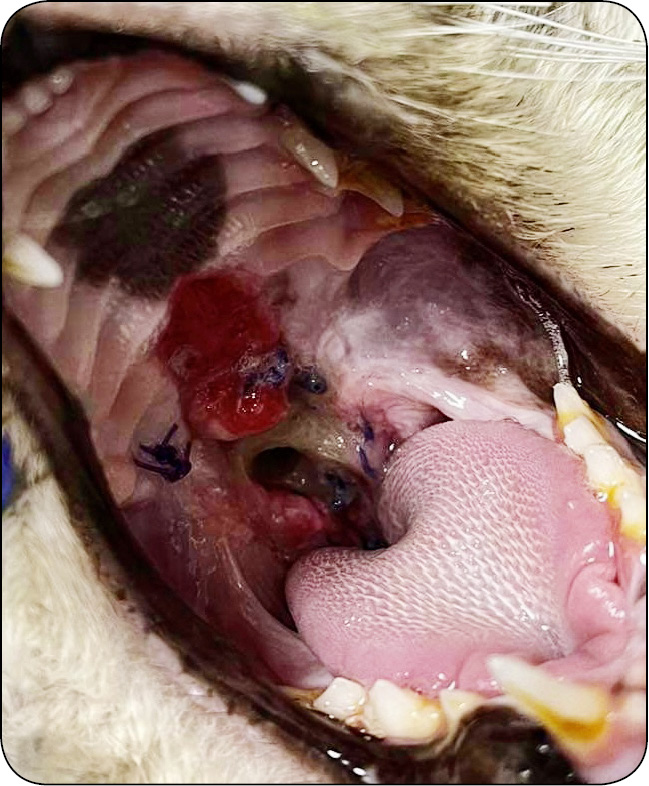

Może wystąpić alergia na użyte szwy lub inne materiały chirurgiczne. W takich przypadkach dochodzi do całkowitego naruszenia rany chirurgicznej, czego konsekwencją jest wybujałe ziarninowanie i zgrubienie w miejscu cięcia, a nawet martwica.

W niektórych sytuacjach szwy mogą ulec zerwaniu lub rozluźnieniu, co może wymagać ponownej interwencji chirurgicznej. Szczególnie u psów brachycefalicznych, które mają pogrubiały język, a także u kotów, których język posiada wyrostki. Ciągła manipulacja językiem może prowadzić do rozwiązania i zerwania szwów. Warto zatem rozważyć zaopatrywanie rany za pomocą pojedynczych szwów.

Krwiak w miejscu operowanym

Dość często przy braku zachowania należytej ostrożności i nieumiejętności specjalisty chirurga może wystąpić krwawienie z obszaru operowanego. Naczynia podniebienne [...]